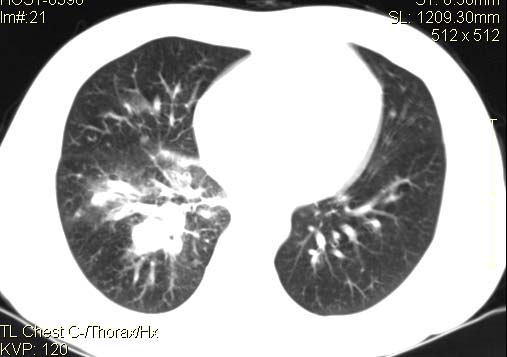

以下是引用qingyuan在2007-4-17 14:19:00的发言:[br]右肺下叶外侧后段胸膜下区节结样病变、分叶、内可见空洞,壁厚薄不均,胸膜凹陷、肺门周围区纹理增粗、僵硬、并近似小结节样改变,肺门区软组织节结、纵膈淋巴结肿大,患者病史长、抗炎治疗无好转炎性改变基本排除,考虑:右肺下叶周围型肺癌伴纵膈及右肺门区淋巴结转移、肺内淋巴管受侵。